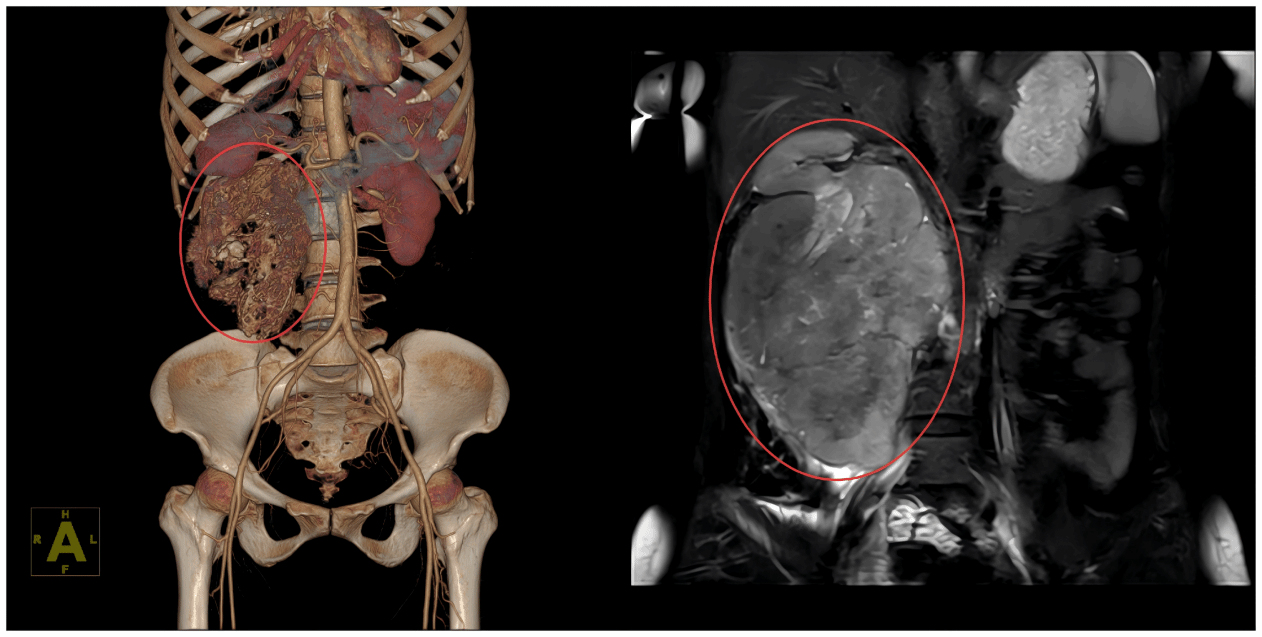

术前影像(左CT右MR)

与此同时,医疗团队利用三维重建技术,在电脑上精准勾勒出肿瘤与周围脏器的立体关系,反复模拟手术入路,并制定了详尽的手术预案和应急预案。麻醉科团队针对患者术中可能出现的循环波动、凝血功能障碍等情况,准备了多项应对措施。